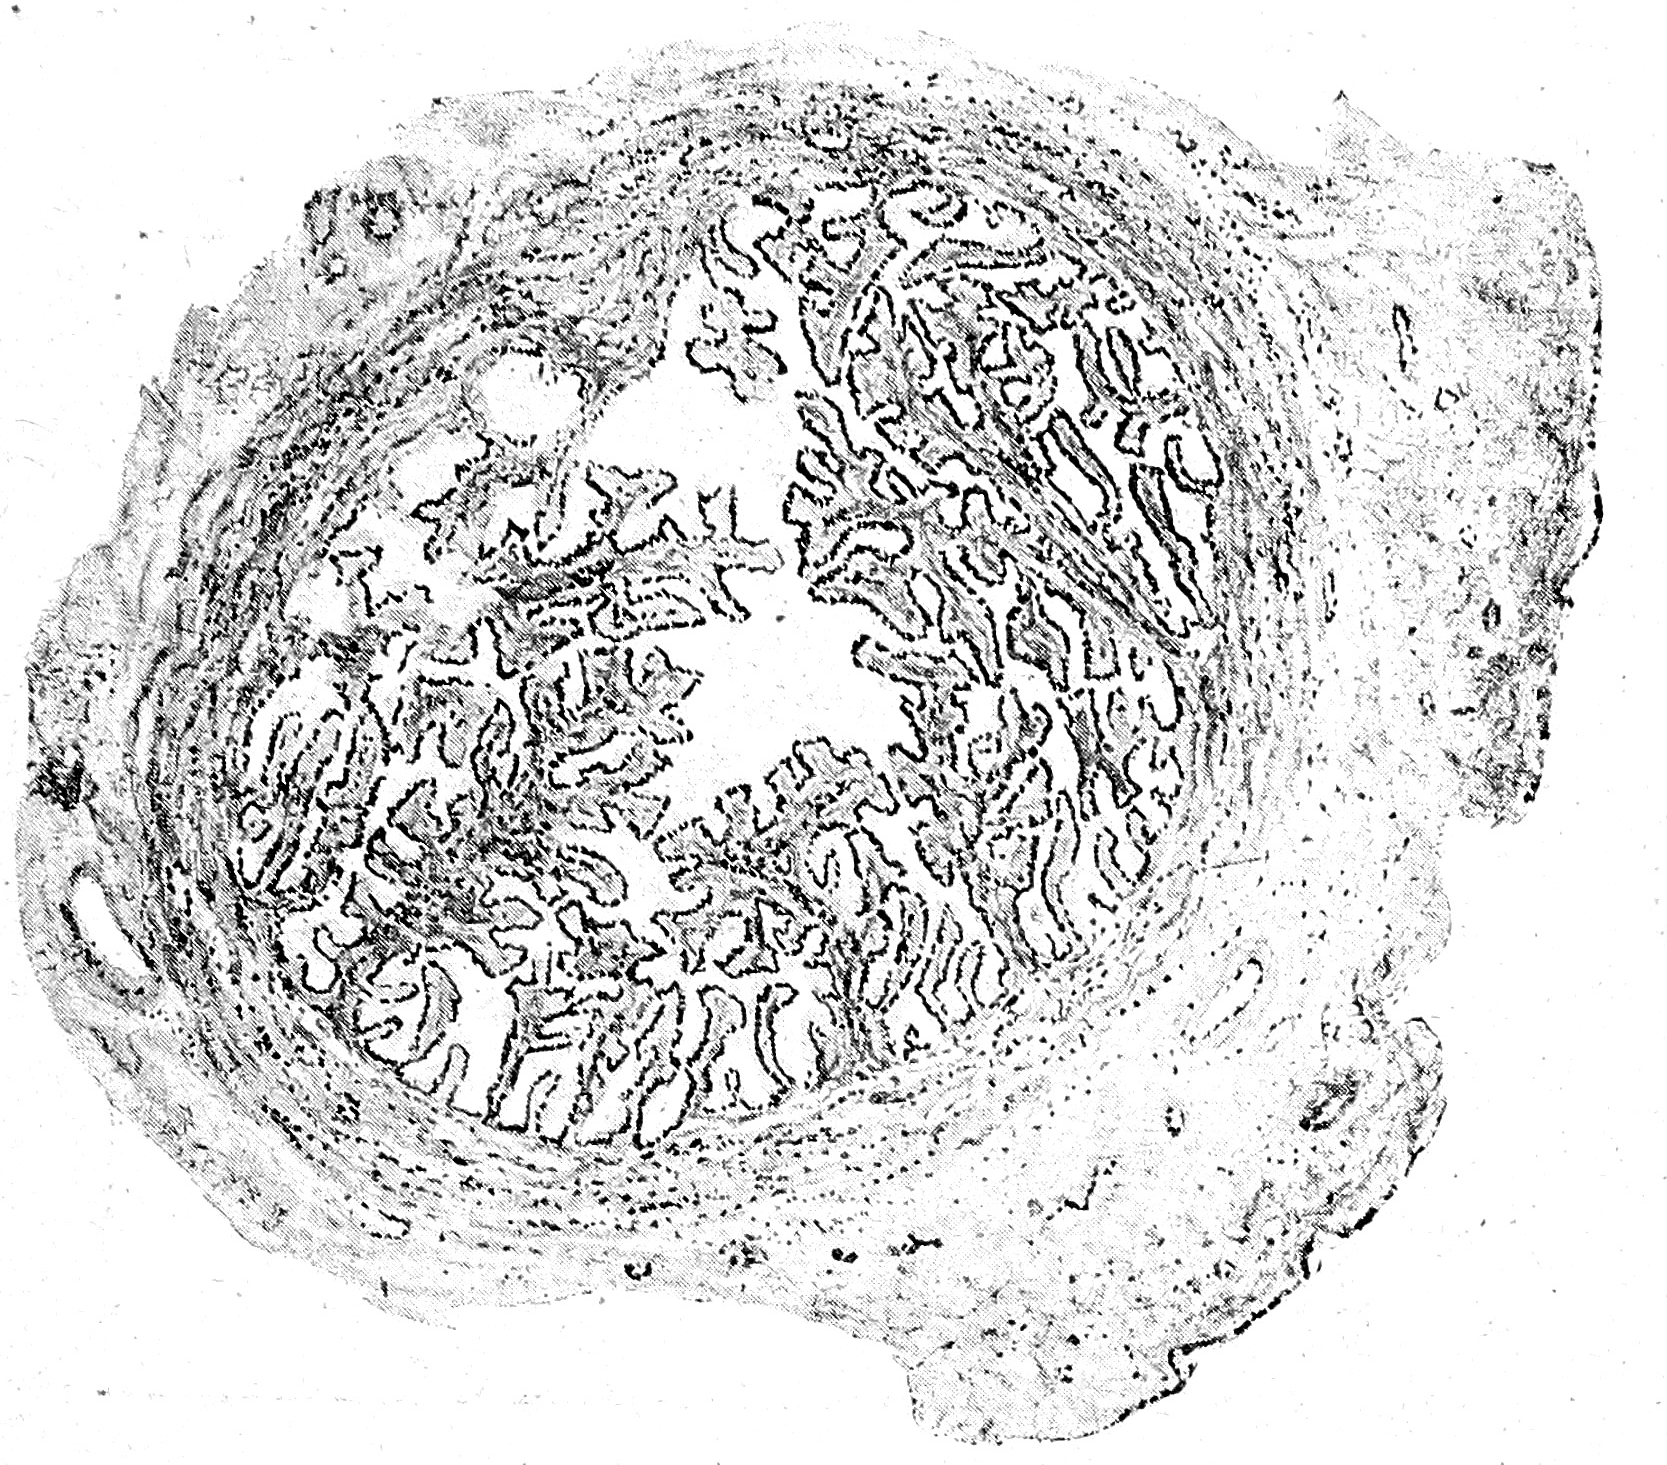

Яичник (рис. 2). Казавшаяся макроскопически гладкою поверхностъ яичника под микроскопом оказалась представляющею значительное количество выпуклостей и углублений. Зародышевый эпителий сохранился местами лишь в этих последних, на большей же части поверхности яичника он вероятно, отслоился при консервировании препарата. Клетки эпителия оказались гораздо более низкими, чем нормально, почти пластинчатыми. Под эпителием располагалась отчетливо выраженная в виде сравнительно бедного клетками слоя волокнистой соединитель той ткани tunica albuginea от которой вглубь подлежащей яичниковой стромы отходили, в радиальном направлении фиброзные перегородки. Располагавшиеся между этими перегородками участки стромы коркового слоя состояли из типичных для последнего веретенообразных клеток, среди которых было заложено значительное количество кровеносных сосудов мелкого калибра. Напротив, ни отчетливо выраженных примордиальных фолликулов, ни каких-либо остатков более зрелых фолликулов, в виде, напр. Glasmembranen corpora albicantia и т. п., в корковом слое, несмотря на самые тщательные поиски, обнаружить было нельзя. Кнутри от коркового слоя располагался богатый более крупными сосудами мякотный слой, строма которого состояла из плотной, бедной ядрами соединительной ткани.

Рис. 2.

Fаllорі’ева труба (рис. 3). В противоположность яичнику груба, при микроскопическом исследовании, оказалась развитой виол не хорошо. На поперечных разрезах просвет ее имел характерный звездчатый вид, благодаря наличности складчатой мукозы. Изнутри просвет яйцевода был выстлан мерцательным цилиндрическим эпителием, под которым различалась tunica propria из богатой клетками соединительной ткани и расположенных продольно пучков гладких мышц (musculaiis mucosae). Кнаружи лежал внутренний циркулярный и наружный продольный слои мышц, среда которых пробегала масса сосудов различного калибра, а дальше располагался слой рыхлой подбрюшинной соединительной ткани переходившей в соединительную ткань мезосальпинкса и широкой связки. В этой последней, на различном расстоянии от трубы, было разбросано, среди; соединительной ткани, весьма большое количество паровариальных канальцев, среди которых один мог быть почти с несомненностью принят за Gагtnеrʹовский канал (Wоlffʹoв вход).

Рис. 3.

Матка (рис 4). Между тем, как микроскопическое исследование трубы обнаружило значительную степень ее развития, матка, насколько можно было судить по исследованию ее на сериях поперечных срезов,, оказалась еще более рудиментарною, чем яичниц еще миометрий ее, состоящий из переплетавшихся в различных направлениях мышечных пучков, как продольных, так и циркулярных, заложенных в волокнистой, богатой венозными и капиллярными сосудами, соединительной ткани, был-более развит; зато эндометрий, можно сказать, едва намечался,—железы в нем совершенно отсутствовали, покровный эпителий был весьма ниским, клеточной стромы мукозы почти совершенно не было, сама маточная полость ни по раз мерам, ни по очертаниям не представляла никакого сходства с нормальной. По своему строению матка представляла просто остановившийся в своем развитии Мuller’ов ход, составлявший продолжение канала трубы и окруженный в значительном количестве пучками гладких мышц.

Рис. 4.